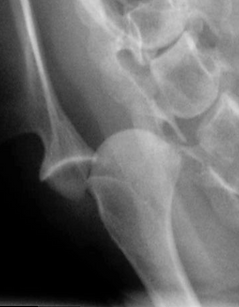

Radiograph showing medial shoulder luxation.

Diagnosis begins with a thorough physical and orthopedic examination. An experienced veterinarian can often suspect the problem based on the way the joint moves and feels. Under sedation or anesthesia, the shoulder may move easily in and out of position, confirming instability.

Radiographs (X-rays) typically reveal the dislocation and may show abnormal joint shape contributing to the issue. In some cases, stress radiographs are taken to demonstrate joint looseness more clearly.